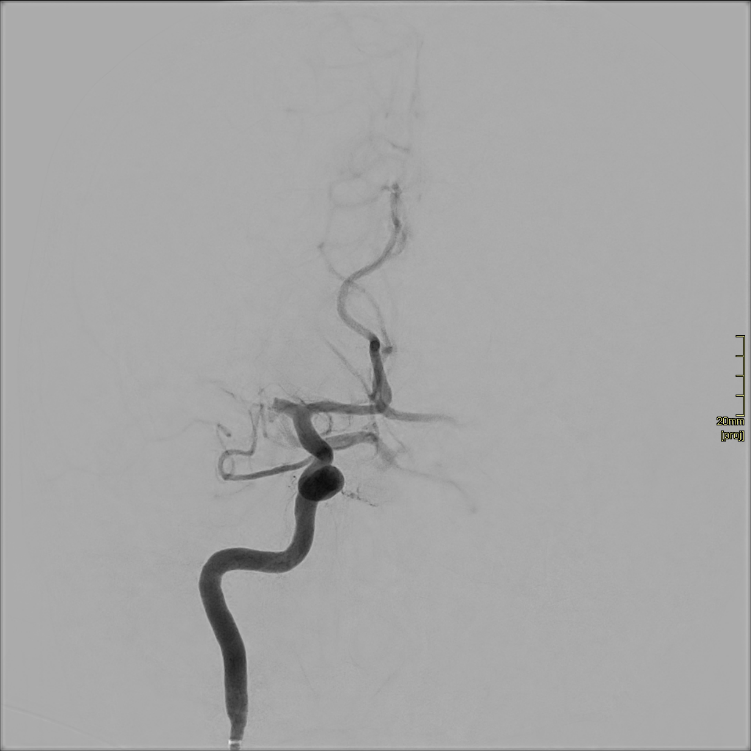

Artère sylvienne droite obturée par un thrombus.

Parmi les traitements disponibles en cas d’AVC ischémique, la thrombectomie est un geste de neuroradiologie interventionnelle qui permet de rétablir, mécaniquement, la circulation sanguine dans le cerveau en retirant le thrombus qui obstrue l’artère. Le radiologue passe par les artères depuis l’aine ou le poignet jusqu’au cerveau.